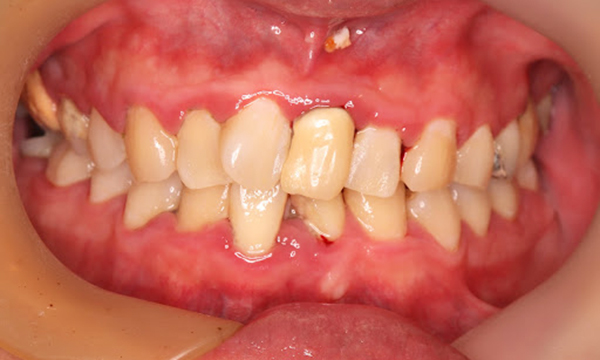

中等度歯周病

特徴

歯肉炎~歯周炎の段階です。

• 腫れや歯磨きの時の出血が頻繁に起こる

• 歯はグラつかない、もしくは少しグラつく

• 口臭がある

• 歯ぐきがムズムズする感じがある

• 歯周ポケットが深くなる

• 歯の周囲組織の破壊が始まる

中等度歯周病の歯ぐきの写真